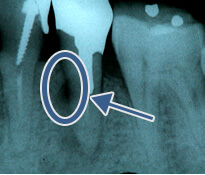

歯の周りのアゴの骨が溶けてなくなり膿が溜まっています(黒く写っている所)